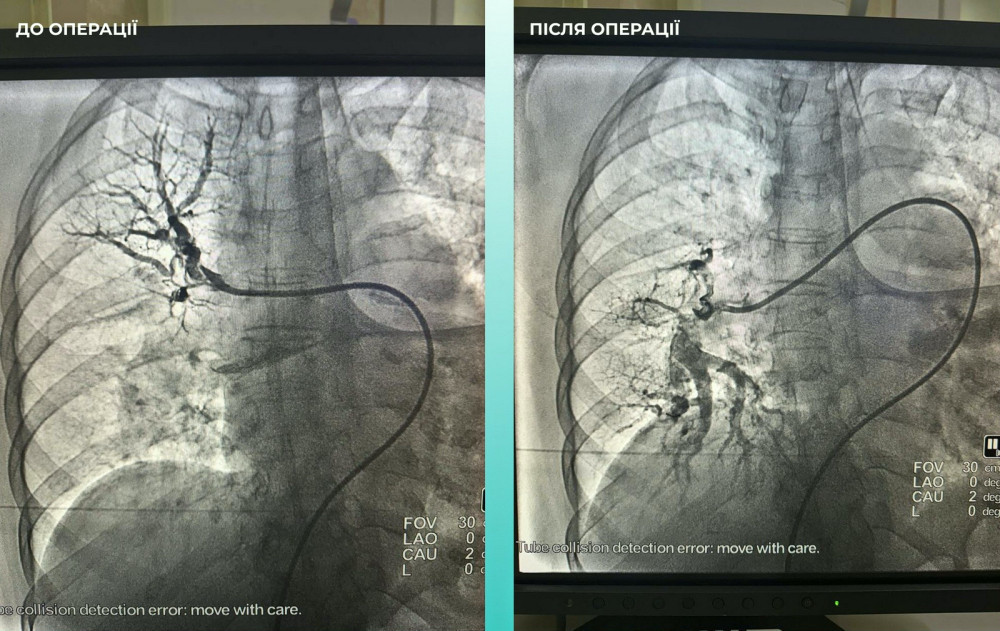

Також лікарі помітили, що у жінки виникають проблеми з диханням, тому провели додаткове обстеження легень. Виявилося, що у неї також є тромбоемболія легеневої артерії.

Мультидисциплінарна команда спеціалістів прийняла важливе рішення — провести одночасну тромбектомію в мозковій та легеневій артеріях.

Операція пройшла успішно. Наразі пацієнтка почувається значно краще: вона в свідомості та може рухати кінцівками.